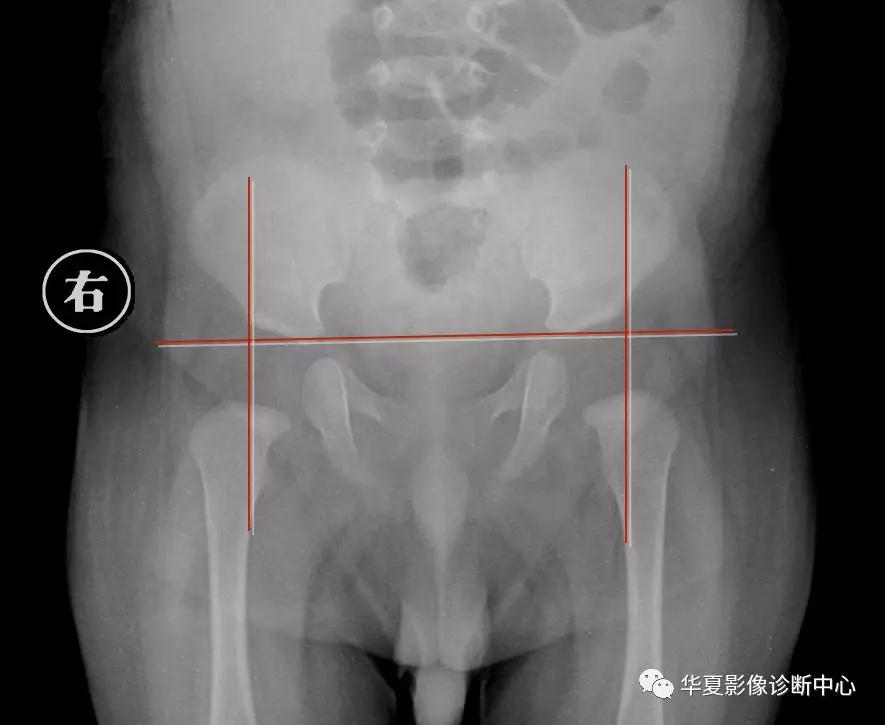

2.骨盆平片测量法

如图所示两侧髋臼Y形软骨连成为Hilg-eneriner线,简称为H线,股骨上端距H线之距离为上方间隙。股骨上端鸟嘴距坐骨支外缘为内侧间隙,正常均值上方间隙为9.5mm,内侧间隙为4.3mm。若上方间隙小于8.5mm,内侧间隙大于5.1mm应怀疑髋关节脱位。若上方间隙小于7.5mm,内侧间隙大于6.1mm可诊断为髋关节脱位,此法简易可靠。

3.Perkin象限

当股骨头骨骺核出现后可利用Perkin象限,即两侧髋臼中心连一直线称为H线,再从髋臼外缘向H线做一垂线(P),将髋关节划分为四个象限,正常股骨头骨骺位于内下象限内。若在外下象限为半脱位,在外上象限为全脱位。

新生儿正常股骨上端鸟嘴状突起位于内下象限内。若在外下象限为半脱位,在外上象限为全脱位。